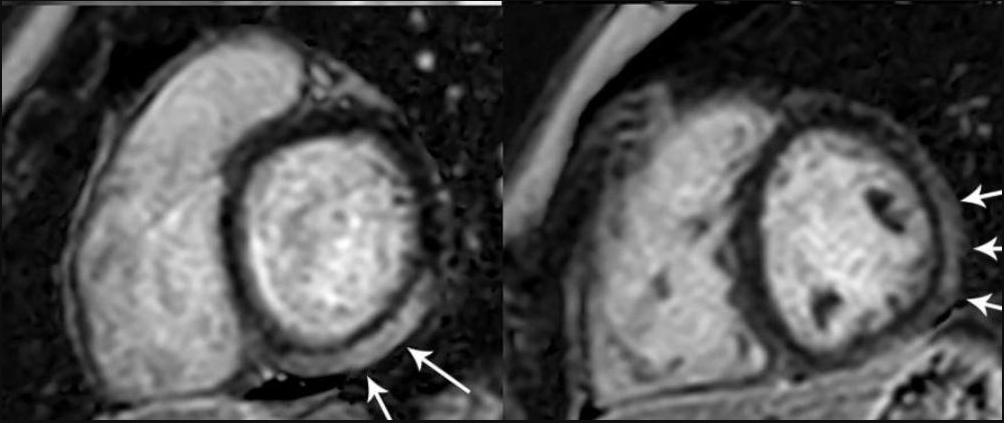

This photo gallery shows the variety of radiological presentations of COVID-19 (SARS-CoV-2) in medical imaging, including computed tomography (CT), radiograph X-rays, ultrasound, echocardiograms and magnetic resonance imaging (MRI). The radiology images show examples of typical COVID pneumonia in the lungs and the numerous complications the virus causes in the body in multiple organs, including the brain, kidneys, heart, abdomen and vascular system.

Ultrasound, especially hand-held ultrasound imaging devices, have become a primary imaging modality for novel coronavirus because of the ease to bag the device and sterilize it after use. CT and mobile X-ray systems are also used as front-line imaging systems for COVID-positive or suspected COVID patients.